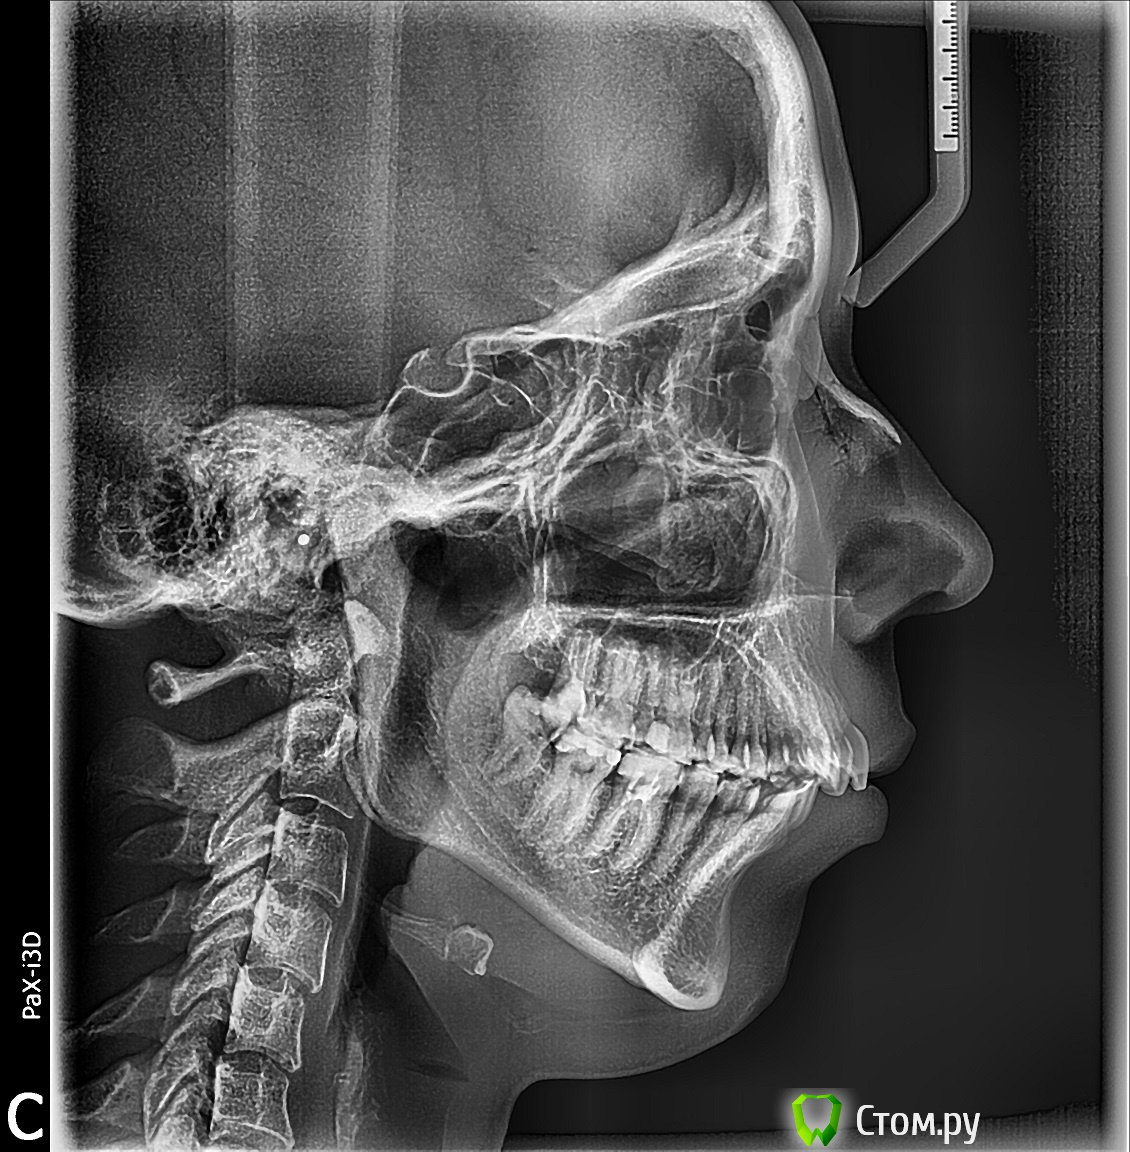

Force Опубликовано 17 августа, 2014 Поделиться Опубликовано 17 августа, 2014 Удаление и дистализация - вряд ли. Проблема больше с нижней челюстью, возможно вовлечен и сустав, судя по рентгенам. Непростая ситуация, возможно, что ортогнатическая коррекция окажется приоритетным вариантом. Но нужна более тщательная диагностика. 1 Ссылка на комментарий